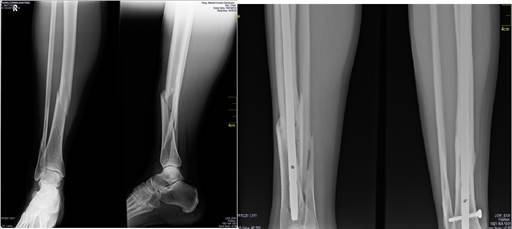

La fijación intramedular es una de las modalidades quirúrgicas más empleadas en fractura de diáfisis tibial, sin tener en cuenta el tercio afectado y se ha visto que la corrección de la alineación en el tercio distal mediante el clavo es mejor, que en el tercio proximal. La mayoría de los clavos intramedulares actuales tienen la posibilidad de fijarse en múltiples planos y distancias (de forma aproximada a 1,5 centímetros del extremo distal del clavo), lo que permite lograr la estabilidad adecuada, aún en la coexistencia de algunas lesiones con extensión intraarticulares, como las no desplazadas, y de fracturas del tobillo no contiguas (Figura 1). 18,19,20